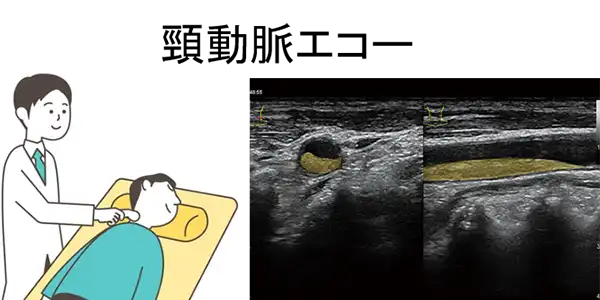

当診療科で行う主な検査には、頸動脈エコーでプラークの有無を調べる方法や、手と足に血圧計のマンシェットを巻いて足の血流低下の有無や動脈の硬さを調べるABI(Ankle Brachial Index)・PWV(Pulse Wave Velocity)があり、いずれも侵襲がなく、簡単に行える検査です。